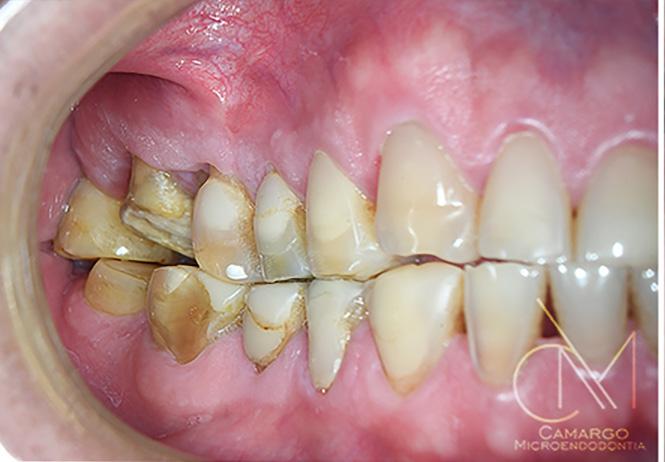

Este caso reporta los detalles de un trata miento periodontal regenerativo de los dientes 11 y 12 (sistema FDI) con movili dad severa y absceso periodontal. La pa ciente era una mujer de 27 años de edad

sin antecedentes contributivos ni aler gias conocidas, y que no estaba tomando medicamentos.

La paciente había comenzado un trata miento ortodóncico con un alineador transparente 6 meses antes de acudir a mi consulta. El objetivo del tratamiento orto dóntico era corregir una maloclusión cla se II de Angle con una moderada separa ción de los incisivos superiores, resalte (overjet) aumentado y proclinación de los incisivos superiores. Después de 6 meses de tratamiento, con cambios semanales de los alineadores creados por ordenador, la paciente desarrolló un absceso alrede dor del diente 12 y fue derivada a un endo doncista par drenar la lesión. Los dientes 11 y 12 se diagnosticaron como insalvables,

con profundidades de sondaje de 15 mm localizadas y movilidad de clase III. La tomografía computarizada de haz cónico (CBCT) y la radiografía periapical mostra ban pérdida de las paredes vestibular y palatina. No obstante, los dos dientes te nían un buen aporte sanguíneo, como se constató en la prueba de vitalidad pulpar. La paciente quería una segunda opinión y fue derivada a nuestra consulta.